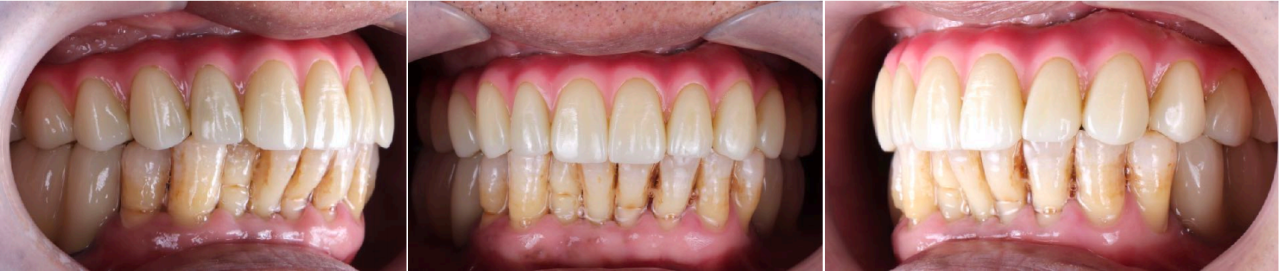

即刻修复3个月后:

上颌边缘骨稳定,行下颌后牙区种植,下颌植入4颗中科安齿种植体

即刻修复5个月后:

边缘骨稳定,上下颌同期行永久修复

永久修复3年随访:

上下颌边缘骨稳定,零骨吸收

通过修复后口内照观察到,美学效果良好,无基台种植体配合性能相关的周围炎。通过医学影像观察到,修复三年后种植体周围无骨吸收,患者非常满意。